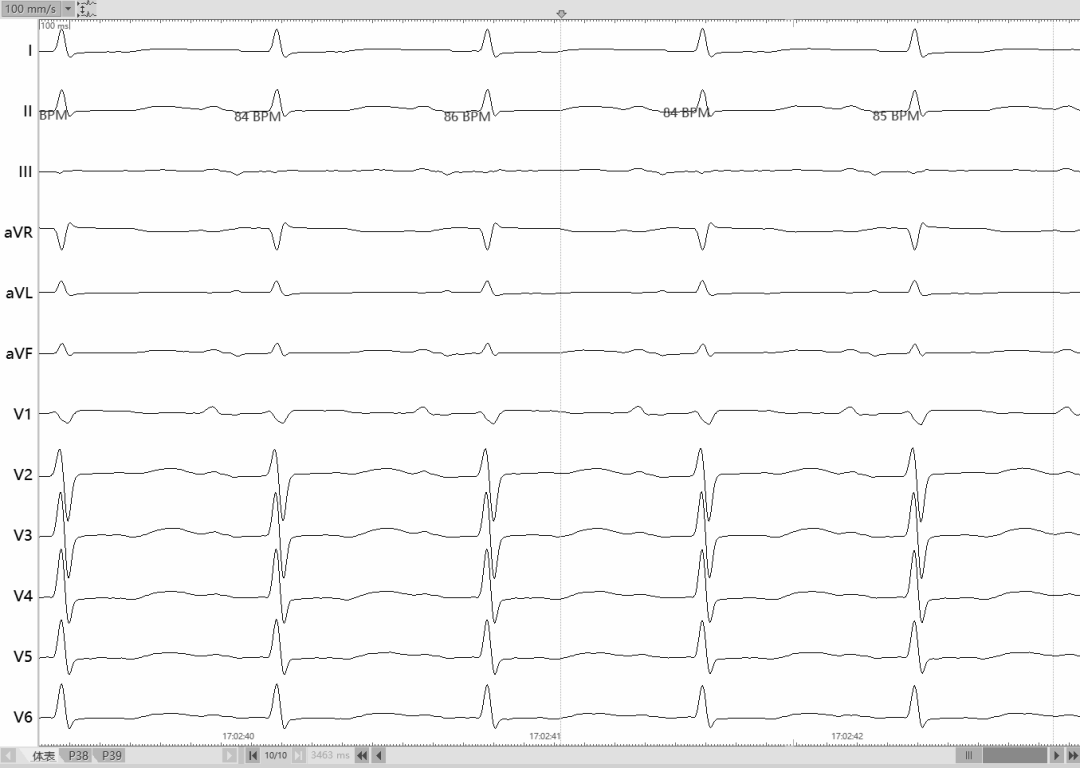

术后体表&腔内心电图